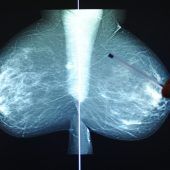

Die Wirksamkeitsstudie zur Brustkrebsfrüherkennung wurde vom Gesundheitsministerium genehmigt.